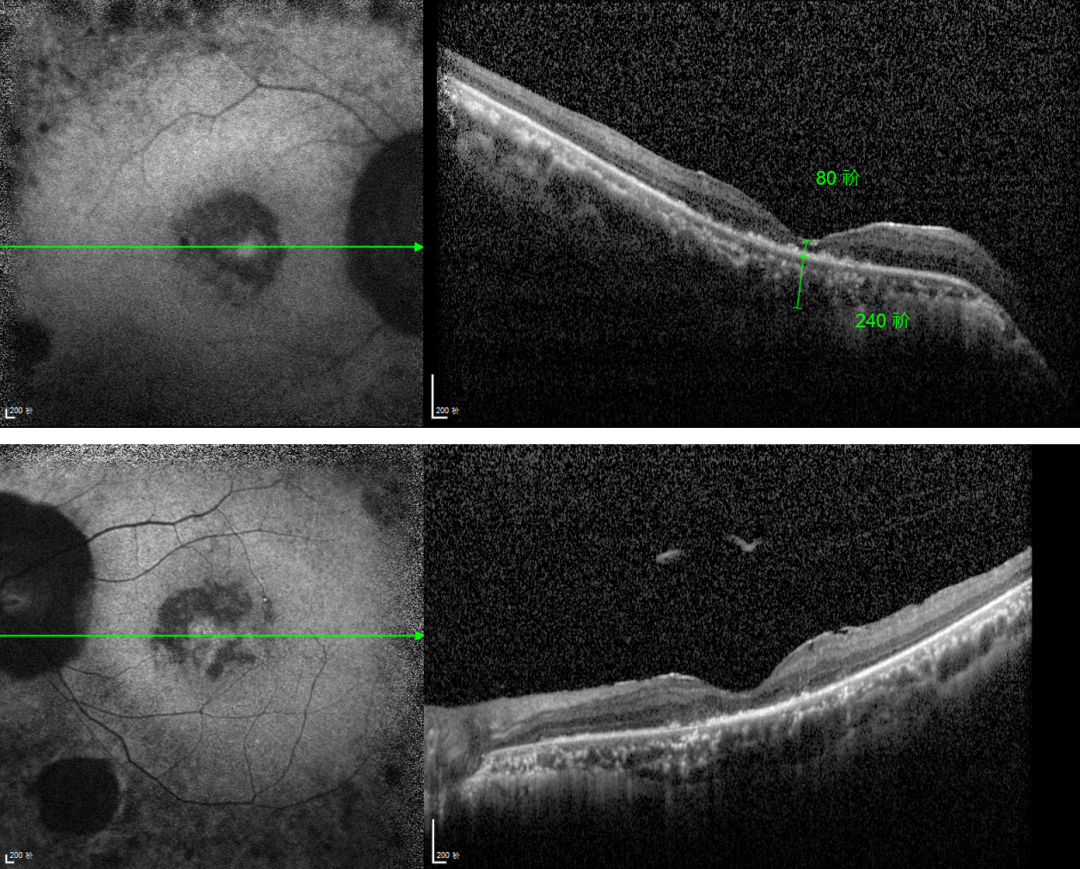

RP的診斷主要依靠眼底檢查、視野檢查、視網(wǎng)膜電圖(ERG)和基因檢測。眼底檢查可見典型的"骨細(xì)胞樣"色素沉著,ERG顯示視網(wǎng)膜功能下降,基因檢測可確定具體的突變基因。

視網(wǎng)膜色素變性